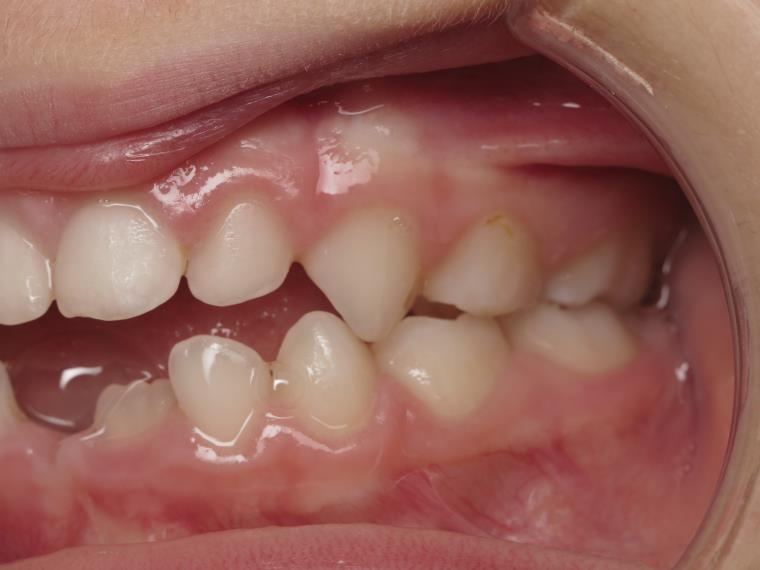

14 béance inversé gauche 5 ans

inversion postérieur coté droit et espace entre l'arcade du haut et du bas (béance)

appareillage mobile pendant 5 mois